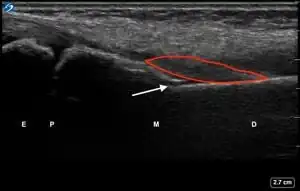

| 3 | Periosteal hematoma[14][15] | ![]() Ultrasound view of periosteal hematoma (area inside red flattened oval) adjacent to cortical break fracture (shown by arrow). E = epiphysis; P = physis; M = metaphysis; D = diaphysis. | |